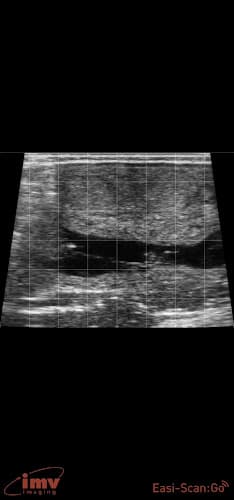

Veterinary Services The practice specializes in Ultrasound.

Ultrasound equipment enables examination of internal organs and soft tissue structures.